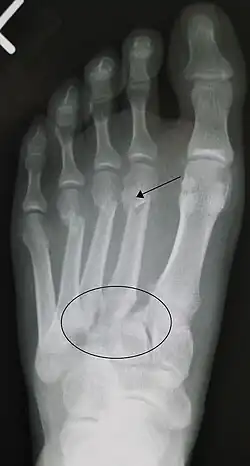

Lors d'une blessure traumatique à haute vélocité au milieu du pied, le diagnostic d'une entorse de Lisfranc doit être évoqué. Face à une telle blessure, la suspicion clinique doit être élevée. Dans certains cas, on peut noter à l'examen physique une plaie sus-jacente et une compromission de l'apport sanguin au pied distal. On note une déformation du milieu du pied et des anomalies évidentes à la radiographie. La trouvaille radiographique classique est un espace entre la base des premier et deuxième orteils[9].

Le diagnostic est plus difficile dans le cas de traumatismes à faible énergie, notamment dans les sports. À l'histoire, le patient peut se présenter seulement avec un inconfort à la mise en charge et un léger gonflement de l'avant-pied ou du milieu du pied. Des ecchymoses de la voûte plantaire ont été décrites comme diagnostiques dans ces circonstances mais pourraient bien être absentes[10]. En règle générale, la radiographie conventionnelle du pied est utilisée avec des vues standard sans mise en charge, complétées par des vues avec mise en charge, qui peuvent démontrer un élargissement de l'intervalle entre les bases du premier et deuxième orteils lorsque les vues initiales ne montrent pas d'anomalie. Les radiographies dans de telles circonstances ont une sensibilité de 50% sans mise en charge et de 85% avec mise en charge[11].